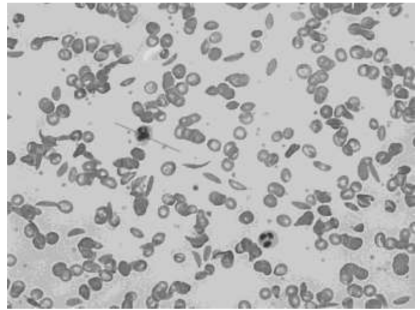

20. Sickle cell anemia (allele a) is a disorder where the RBCs stretch out and become thin as opposed to the round normal (allele A) RBCs. A person who is homozygous for normal RBCs marries a person who is heterozygous for sickle cell RBCs.

What is the probability of the offspring being homozygous for the sickle cell trait?

Blood from one of the offspring was checked, and the microscopic image of its RBCs is shown below.

What is the genotype of this individual?

(c) Based on the image shown, explain the type of dominance exhibited by the sickle cell allele?

Ans:

- Probability of offspring being homozygous for sickle cell anemia – 0%

- Heterozygous (Aa) for sickle cell anemia.

- co-dominance – as both parental alleles are expressed in the offspring